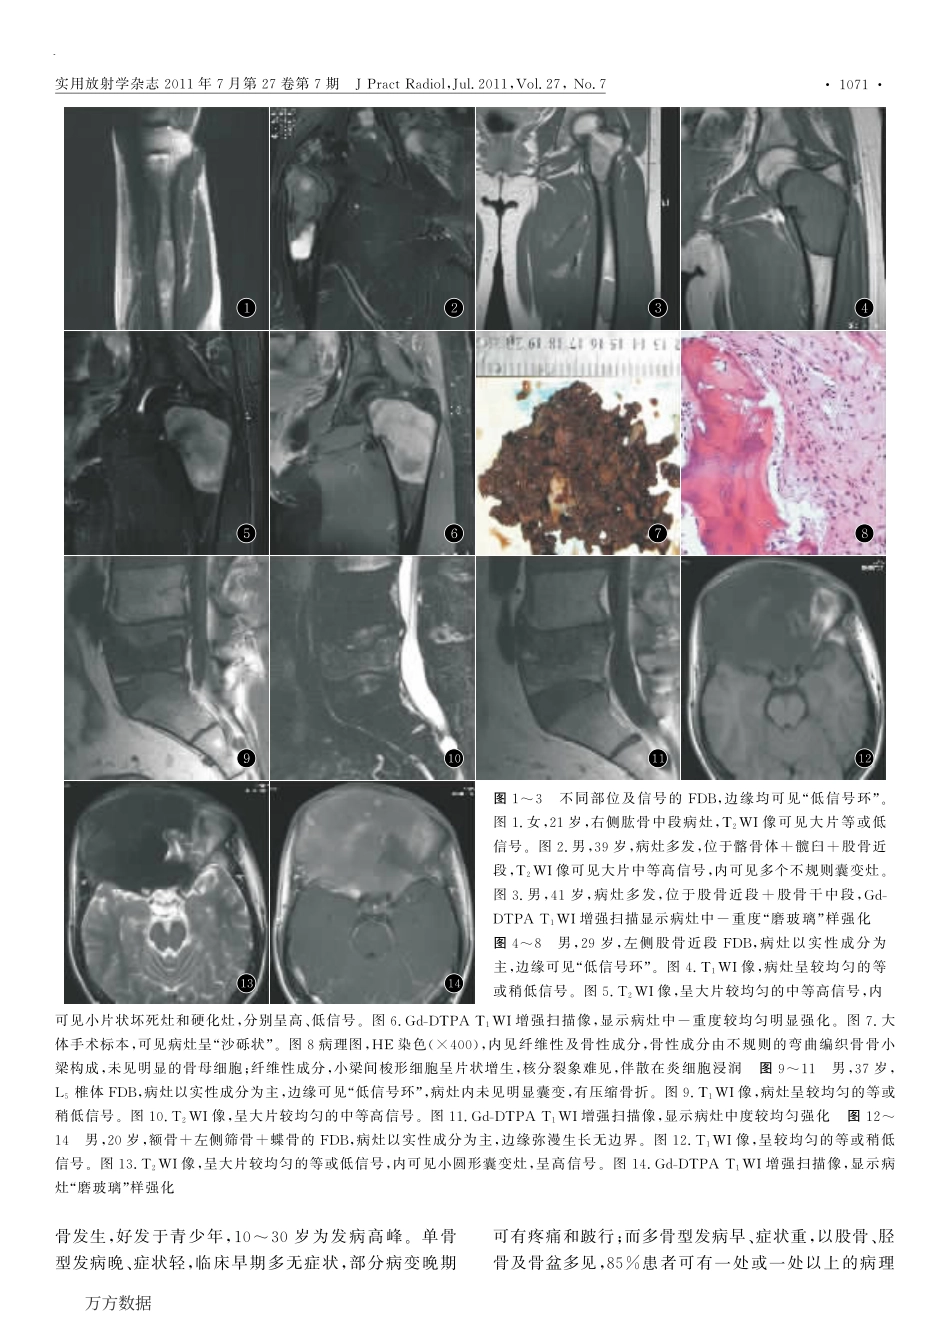

作者简介:陈任政(1971-),男,广东省阳江市人,硕士,副主任医师,主要从事影像诊断工作。通信作者:彭旭红,Email:pxh2005@163.com骨纤维结构不良的MRI表现陈任政1,张雪林2,曲华丽2,王建平2,苍鹏2,彭旭红2(1阳江市人民医院放射科,广东阳江529500;2南方医科大学附属南方医院影像诊断科)摘要:目的探讨骨纤维结构不良(FDB)的MRI特征,以提高对该病诊断和鉴别诊断的能力。方法30例经病理证实的骨纤维结构不良,其中颅面骨11例21个病灶,四肢长骨17例19个病灶,腰椎椎体2例2个病灶,将60%以上病例或病灶所拥有的表现定义为常见表现。结果(1)颅面骨FDB常见表现:病变多发(72.73%),好发于额骨(72.73%)与筛骨(63.64%),以实性成分为主(100%),弥漫生长无边界(95.24%),T1WI实性部分等或稍低信号(80.95%);T2WI实性部分均匀等、低信号(71.43%);实性部分中-重度均匀强化(100%);病灶内有小圆形囊变(66.67%)和小片状坏死(90.48%),无高信号出血(76.19%),无软组织肿块及边缘水肿(100%)。(2)四肢长骨与腰椎FDB常见表现:病变单发(89.47%),好发于股骨(63.15%),以实性成分为主(95.24%),边缘有“低信号环”(100%)。T1WI实性部分等或稍低信号(76.19%),T2WI实性部分中等高信号(71.43%),实性部分中-重度较均匀强化(90.48%)。病灶内有类圆形或不规则囊变(66.67%)或小片状坏死(90.48%),无高信号出血(100%)及软组织肿块(100%),边缘无水肿(90.48%)。结论四肢长骨与腰椎的FDB表现类似,与颅面骨FDB在病变边界、囊变形态上表现有所不同,其MRI常见表现大部重叠。关键词:骨;骨纤维结构不良;磁共振成像DOI:10.3969/j.issn.1002-1671.2011.07.026中图分类号:R681;R445.2文献标志码:A文章编号:1002-1671(2011)07-1069-05MRIFeaturesofFibrousDysplasiaofBoneCHENRenzheng,ZHANGXuelin,QUHuali,WANGJianping,CANGPeng,PENGXuhong(DepartmentRadiology,YangjiangCityPeople’sHospital,Yangjiang,GuangdongProvince529500,China)Abstract:ObjectiveTostudyMRimagingfindingsoffibrousdysplasiaofbone(FDB),sothattoimprovethediagnosticaccuracyanddifferentialdiagnosisofthisdisease.Methods30patientswithhistologicallyprovenfibrousdysplasiaofbonewereinvestigatedbyMRI(T1WI,T2WI,intravenousgadoliniumadministration).Thecommonsignsweredefinedasthesignsappearedin60%ormorecases.Results(1)ThecommonsignsofFDBincraniofacialbonesincluded:multiplelesions(72.73%),locatedinfrontale(72.73%)andethmoid(63.64%),predominantlysolidportionofthelesions(100%),diffusiongrowthwithindefinitivemargins(95.24%),smallroundcysticdegeneration(...